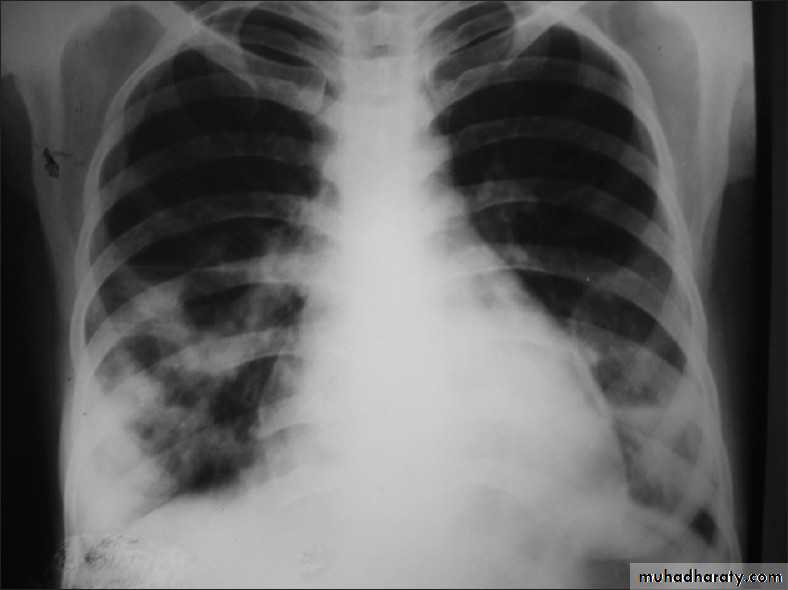

A chest X-ray is usually sufficient to confirm the clinical diagnosis of pneumonia.

In lobar pneumonia, a homogenous opacity localized to the affected lobe or segment usually appears within 12 – 18 hours of the onset of illness.

Chest X-ray helps in:• Differentiating CAP from other diagnosis

• Provide information about severity (cavitation and multilobar involvement)

• Detects complications (pleural effusion or abscess formation).

• It can occasionally suggest an aetiological agent (pneumatocoele in Staphylococcus aureus pneumonia).